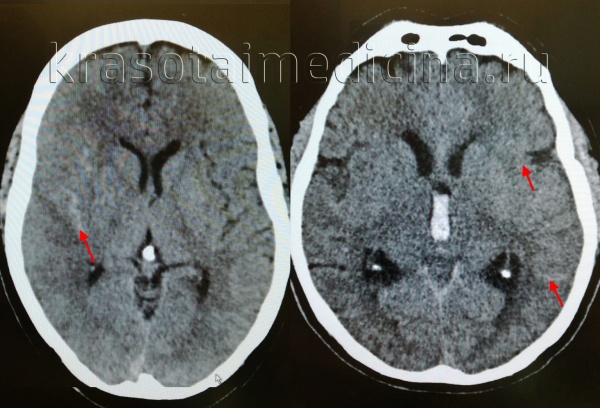

о Гиперденсное скопление крови в одной или нескольких соседних бороздах дорсолатеральной конвекситальной поверхности головного мозга на бесконтрастной КТ

(б) Бесконтрастная КТ, аксиальный срез: у женщины 28 лет с интенсивной головной болью, возникшей после родов, определяется ограниченное субарахноидальное кровоизлияние, локализующееся над конвекситальной поверхностью правого полушария.

• Часто отмечается слабо гиперденсное скопление крови в одной или нескольких соседних бороздах конвекситальной поверхности головного мозга

• Локализация в базальных, перимезенцефальных цистернах не характерна